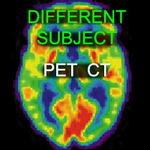

The Different Subject PET/CT collection contains cases of registering PET/SPECT/CT images from different subjects, e.g. aligning a SPECT perfusion atlas with an MRI.